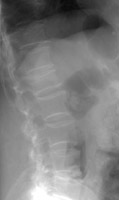

Compression fractures of the spine are common in elderly and osteoporotic patients. They result from anterior or lateral flexion. The typical appearance is loss of height of the anterior aspect of the vertebral body with preservation of the posterior elements and generally the posterior aspect of the vertebral body. On the frontal view, there may be subtle deviation of the paraspinous line due to edema. Differentiation from a pathologic fracture of the spine due to a metastasis is usually of clinical concern, but simple compression fractures are usually due to osteoporosis.

- Click on the image for a larger versionALateral radiograph of the lumbar spine. This shows an osteoporotic compression fracture of the L1 vertebral body.